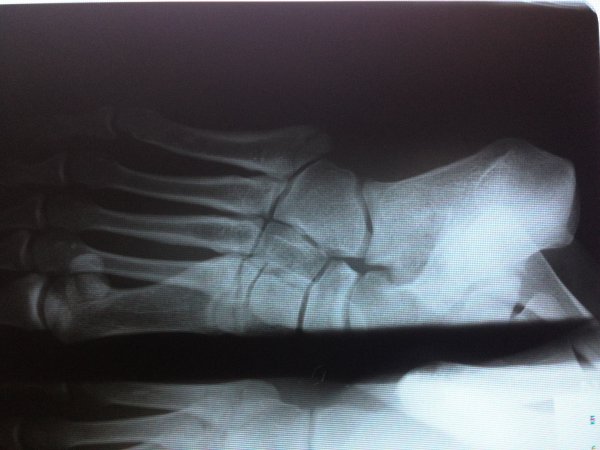

DOKUMENTACJA MEDYCZNA GAMROTA I WŁODARKA

Dokumenty dotyczące kontuzji zawodników KSW.